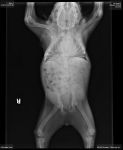

In fact, the arms-raised posture you see in this video is a defensive one used when a loris is frightened. This intimidated loris is feeling uncomfortable and is raising its arms for better access to the brachial glands in its armpits. It can lick these areas to create a “venom” which can damage other lorises and cause a serious reaction in humans.